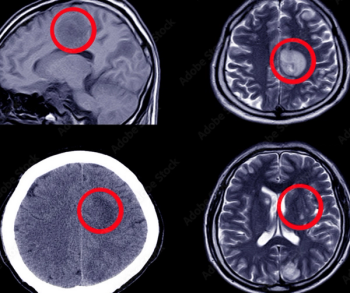

What does the CT reveal?

What is your diagnosis?